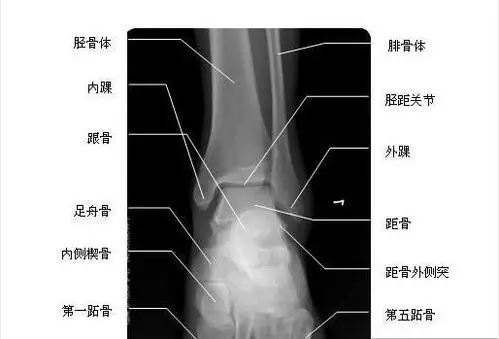

脚踝也可以叫踝关节,是脚与腿相连的部位,包括7块跗骨加上足部的跖骨

距骨是一个不规则骨,上方,下方,前方都有骨相邻,是足和踝关节的承接